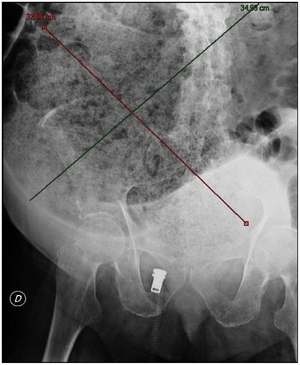

Plain abdominal X-ray showing a huge fecal impaction extending from the pelvis upwards to the left subphrenic space and from the left towards the right flank, measuring over 40 cm in length and 33 cm in width.